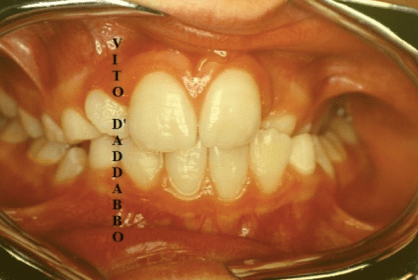

In una bocca che chiude correttamente i denti dell’arcata superiore sono collocati più esternamente rispetto ai corrispondenti dell’arcata inferiore. Nel morso inverso accade il contrario: in quello laterale sono i denti inferiori laterali a chiudere esternamente.

Questa malocclusione è il più delle volte dovuta a un mascellare piccolo, come nel caso riportato, dove manca anche lo spazio per l’incisivo laterale permanente di sinistra. I morsi incrociati vanno corretti precocemente perché possono provocare gravi asimmetrie del viso.

dopo